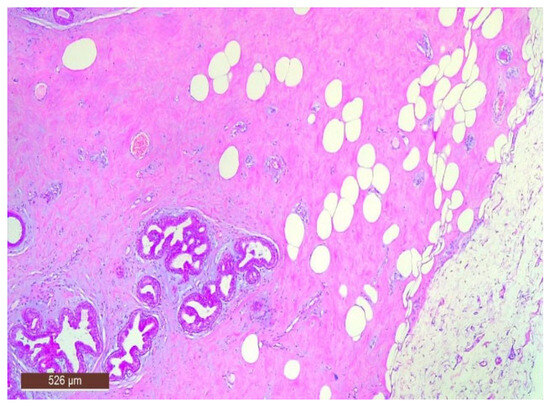

On microscopic examination, a hamartoma may exhibit three predominant components: glandular, fibrous and adipose (Figure 7). Epithelial components such as ducts and lobules are generally normal, featuring a single layer of epithelium overlying the myoepithelial cells. The fibrous component was composed of connective tissue stroma with a delicate connective tissue capsule (Figure 8). Additionally, the ducts within the hamartoma may display apocrine metaplasia (Figure 9).

Figure 7. Hamartoma—histological structure (HE ×40).

Figure 8. Hamartoma with fine connective tissue capsule (arrow) (HE ×40).